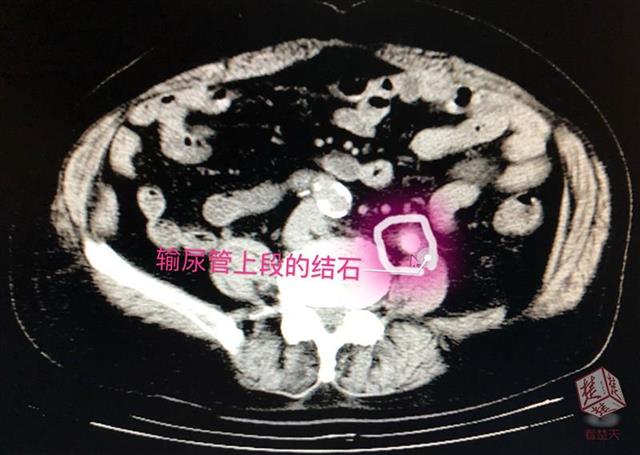

经检查,泌尿外科专家李辉明主任发现,患者左侧输尿管上段被一颗直径约1.2厘米的结石堵住,已出现重度肾积水并感染(肾积脓)。“明明一直在吃排石药,怎么石头还在呢?”老人觉得奇怪。排石药一般都具有利尿、扩张输尿管的作用,服用后原本稳定的肾内结石会随尿液下排,很易在输尿管狭窄处产生滞留,李辉明解释,正是由于赵爹爹的结石卡在了输尿管上段,随着尿液中结晶成分不断附着,结石越变越大,便形成了梗阻。时间长了,尿液排不出去,把肾脏憋成了一个只进不出的“水囊”,目前,积水已达200ml,老人出现的腰痛、高烧、血尿等病症便是结石梗阻产生的急性症状。